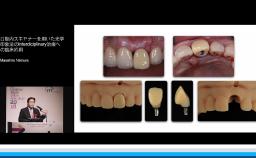

本講演では,上顎洞底挙上術の一手法である側方開窓術の術前臨床的判断基準,術式詳細,臨床経過,CBCT所見,術後偶発症,文献的考察から,開窓部へのバリアメンブレン設置を整理する.

上顎洞底挙上術(側方開窓)におけるバリアメンブレンの理論が理解できる。